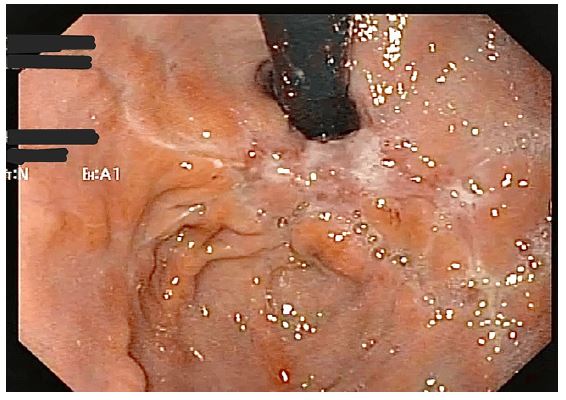

During his stay in the intensive care unit, he was treated with ceftriaxone and azithromycin, however his white blood cell count increased (Table 1), and clinical condition worsened, requiring an escalation of the antimicrobial spectrum to piperacillin and tazobactam (4,5 g qid) over the following two weeks, and later meropenem (1G tid) associated with teicoplanin (400 mg sid). In addition, the patient developed oliguria and renal dysfunction secondary to septic shock, requiring renal replacement therapy with hemodialysis. After 2 weeks in ICU, the patient developed upper gastrointestinal bleeding, with melena and a drop in hemoglobin. An upper digestive endoscopy was requested, which showed an ulceroinfiltrative lesion in the fundus and gastric body, measuring approximately 70 mm, and no signs of active bleeding and no need for endoscopic therapy (Figure 1). Biopsies of the lesion were performed, which demonstrated active, chronic ulcerated inflammation, with numerous short and irregular segments of hyphae amidst necrotic debris, without cellular atypicality, findings suggestive of mucormycosis (Figure 2).

Figure 1: Upper digestive endoscopy, demonstrating an infiltrative ulcer lesion, covered by fibrin, affecting the gastric fundus and great curvature of the gastric body.

After the diagnosis of mucormycosis, by histopathological analysis, treatment with Amphotericin B liposomal (3 mg/kg/day) was chosen for 14 days. After the end of treatment, a new upper gastrointestinal endoscopy demonstrated marked improvement of the gastric lesion (Figure 3), without new episodes of upper gastrointestinal bleeding or other gastrointestinal symptoms. The patient improved clinically from COVID-19, with extubation after 12 days, and discharge from the ICU, with hospital discharge approximately 2 months after admission. Currently, he remains well clinically, undergoing outpatient follow-up.